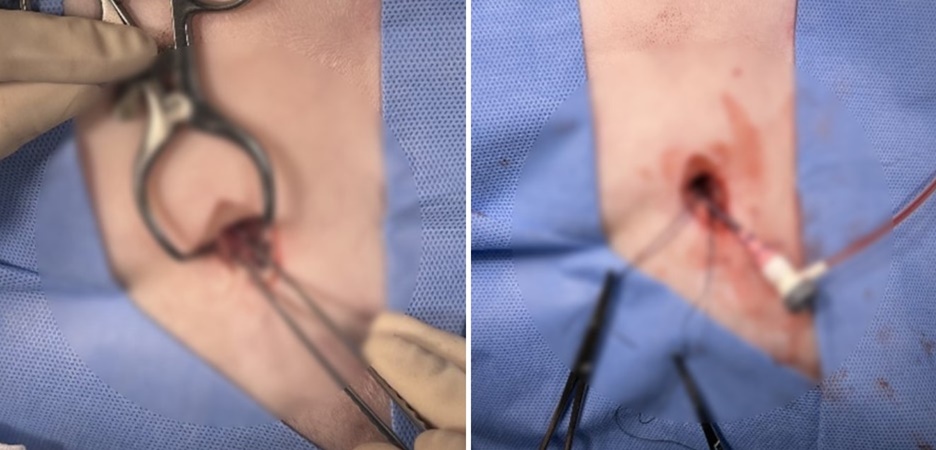

▲ 시술을 위해 대퇴동맥으로 접근합니다. 대략 2-3cm 정도의 절개가 필요합니다. 대퇴동맥을 확보한 뒤 동맥 카테터를 설치하여 고양이 간종양으로 접근할 준비를 합니다.

▲ 고양이 간종양 색전술 시술 후 모습입니다. 개복술에 비해 현저히 작은 접근 부위를 확인할 수 있습니다.

대퇴부를 봉합하고

고양이 간종양 색전술 시술을

마무리했습니다.